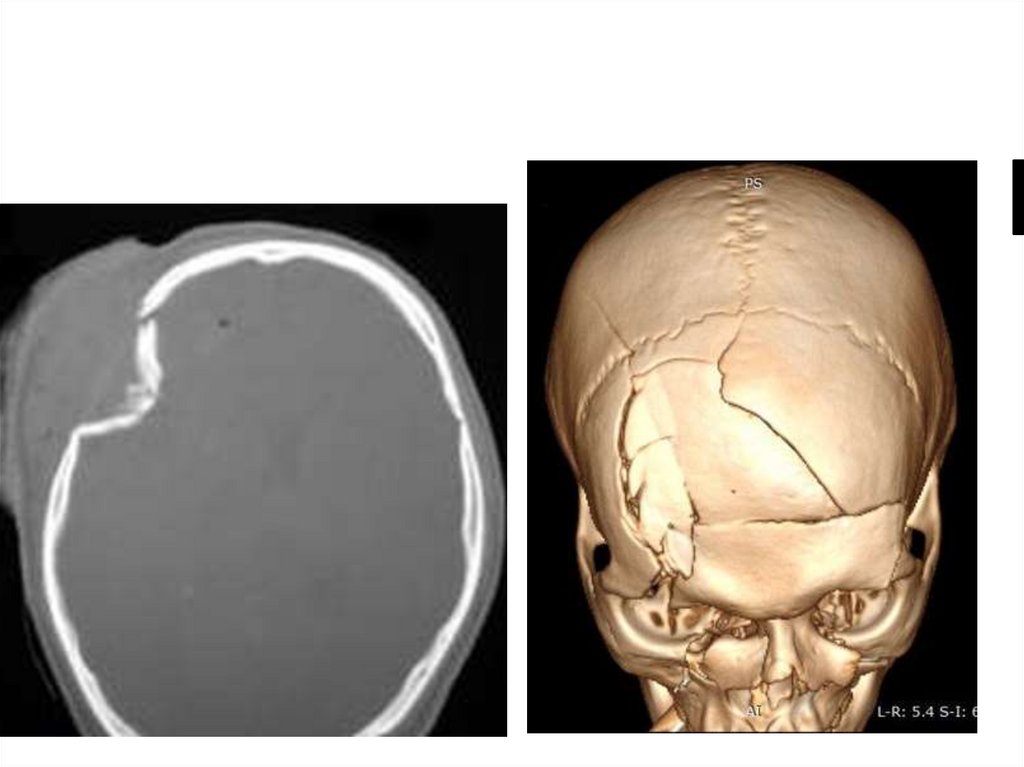

Переломы костей свода черепа

• Линейные

• Оскольчатые:

– Без вдавления (простой)

– Вдавленные

• Импрессионный

• Депрессионный

• Травматическое расхождение швов

13.

Линейный перелом

На рентгенограммах черепа в двух проекциях

линейный перелом правой теменной кости

14.

Вдавленный импрессионный перелом

15.

16.

Вдавленный депрессионный

перелом

17.

Расхождение швов

18.

КТ при черепно-мозговых травмах